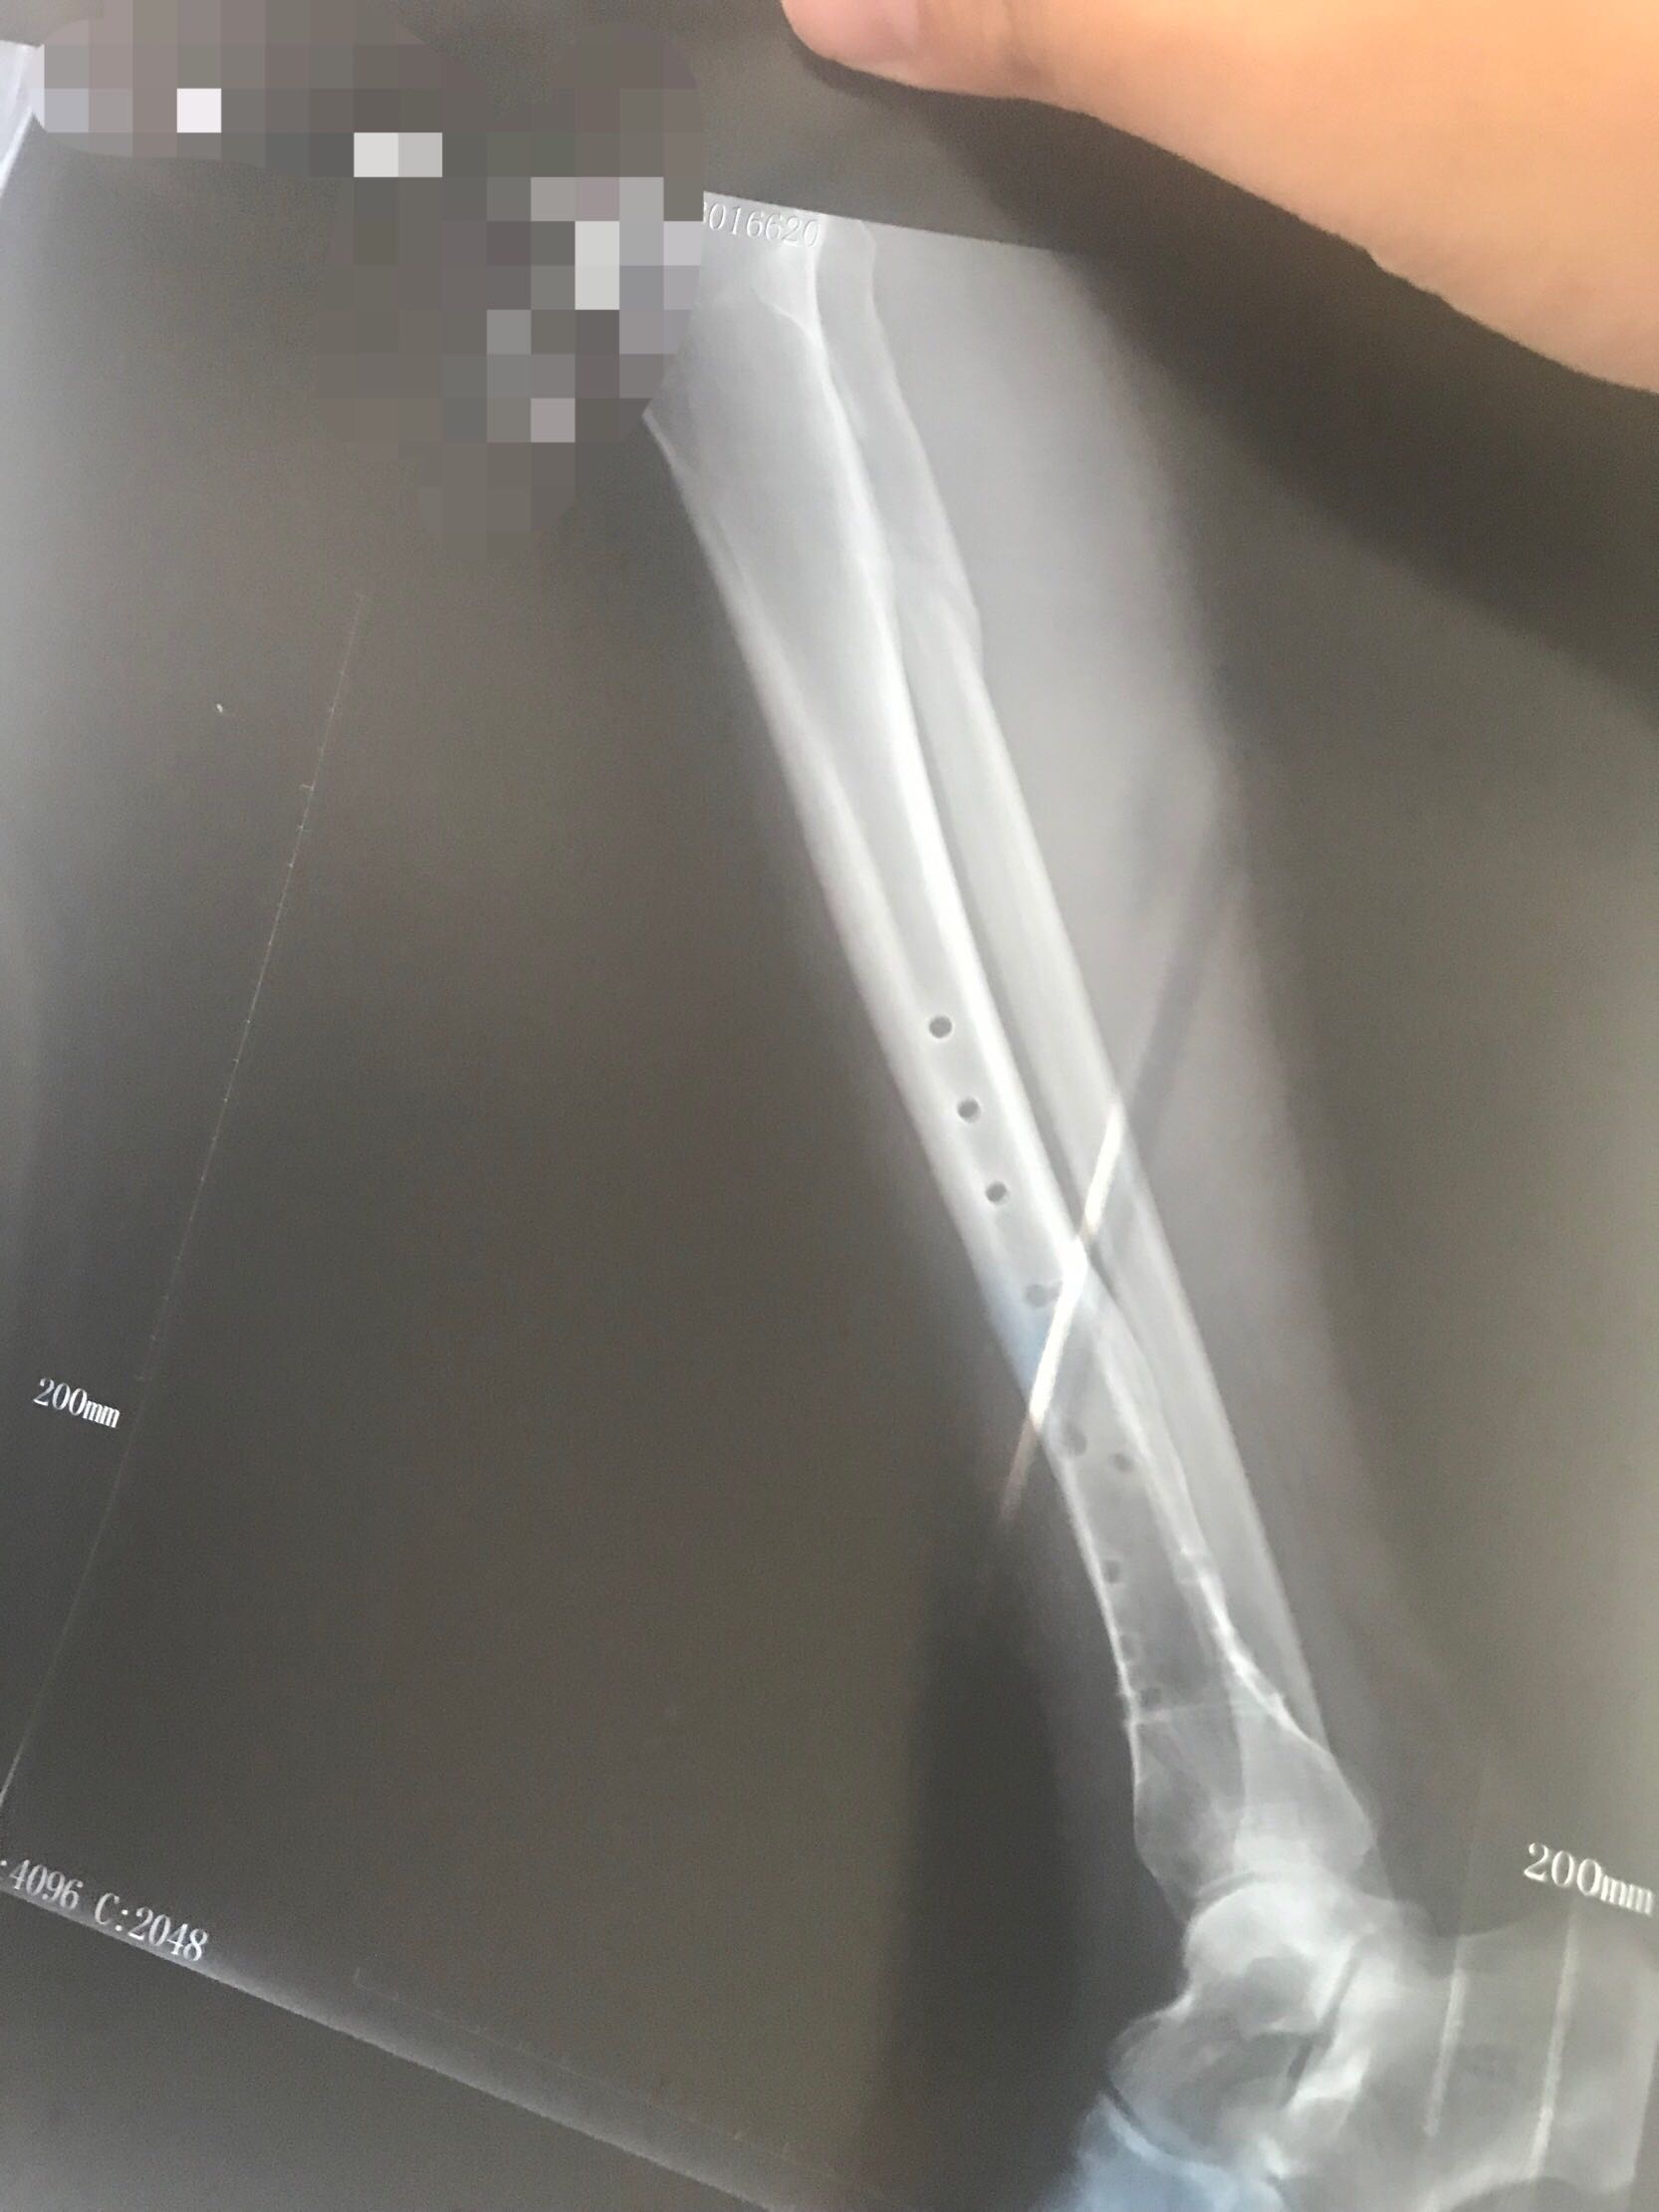

取钢板50天的片子对比,大神们看看长的怎么样?

这是取完钢板的片子。

这是取完钢板50拍的片子。

大神们看看长的怎么样?